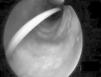

In 15 cases (7.2%), bronchoscopy was carried out in patients under spontaneous breathing conditions or subjected to noninvasive mechanical ventilation in BIPAP mode, and in 193 cases (92.8%) it was carried out in patients subjected to mechanical ventilation. The clinical characteristics of the patients are shown in Table 1, distributed according to whether bronchoscopy was performed under conditions of mechanical ventilation or not. The main indications of fibrobronchoscopy are indicated in Table 2. The predominant indication was diagnostic evaluation, particularly suspected pneumonia, where positive microbiological cultures were obtained in 70 cases (46.4%), followed by therapeutic indications—fundamentally the resolution of atelectasis (percentage resolution rate 71.4%), particularly those caused by central mucus plugging. Fig. 1 shows the endoscopic view of a patient with complete lung atelectasis in which a central mucus plug was aspirated from the right main bronchus.

Percutaneous tracheotomy25,26 is a common practice in the ICU. It produces few complications, though these are potentially serious, including false access routes, pneumothorax, subcutaneous emphysema, transesophageal fistulas, etc. Such problems are mainly due to a lack of visualization of the airway while performing the technique. Bronchoscopic control minimizes the complications of the procedure,27 particularly in patients with difficult anatomical characteristics at neck level. Its use in such cases increases the clinical safety of procedure that is routinely used in the ICU. Fig. 2 shows guide insertion in the tracheal lumen during tracheotomy performed in one of the patients included in the study. The availability of fibrobronchoscopy in the ICU is essential for dealing with the so-called “difficult airway”,28,29 though in practice this is an infrequently applied indication,5,22 since experience in performing the technique is required. The third indication in order of frequency in our series was the management of pulmonary hemorrhage. In such cases bronchoscopy proved useful not only in diagnostic terms but also for treatment purposes in the presence of active bleeding.30,31 There have been descriptions of the plugging of bleeding points by means of a Fogarty catheter32 positioned through the endoscope aspiration canal. The same technique has also been reported using a Swan-Ganz catheter.3 We in turn contribute our experience with the intrapulmonary administration of activated coagulation factor VII instilled through the bronchoscope canal in two life-threatening emergencies involving alveolar hemorrhage refractory to conventional treatment, and which responded favorably to this technique. Nevertheless, this experience must be viewed with caution, since few cases have been described in the literature, and further studies are needed to evaluate such treatment and its efficacy.33,34 Other indications comprised a case of alveolar proteinosis, vocal cord examination in a case of hanging, a case of drowning in sea water in which abundant algae and sand were aspirated through the bronchoscopy canal, a case of chest trauma in which bronchoscopy was used to explore bronchial tree injuries under direct visualization,35,36 and a case of direct intubation guided by the bronchoscope through a tracheal prosthesis, in which intubation initially did not prove possible.